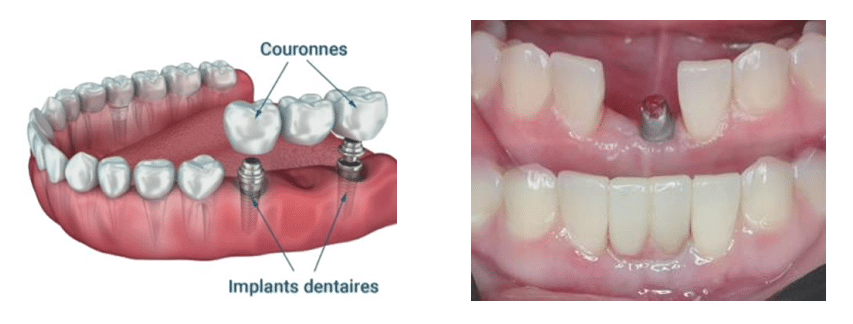

Les bridge implanto-porté :

Un implant peut permettre la réalisation d’une restauration unitaire ou plurale.

Grâce au bridge implanto-porté, il est parfois possible de poser deux implants pour remplacer trois dents, ce qui constitue une solution mécaniquement soutenable et économiquement plus avantageuse.

Principes de conception :

-

Il est préférable que l’ensemble des piliers du bridge (piliers extrêmes et intermédiaires) soient implantaires.

-

Deux configurations existent :

-

Bridge traditionnel sur implants (image de gauche).

-

Bridge en extension (cantilever) sur implants (image de droite).